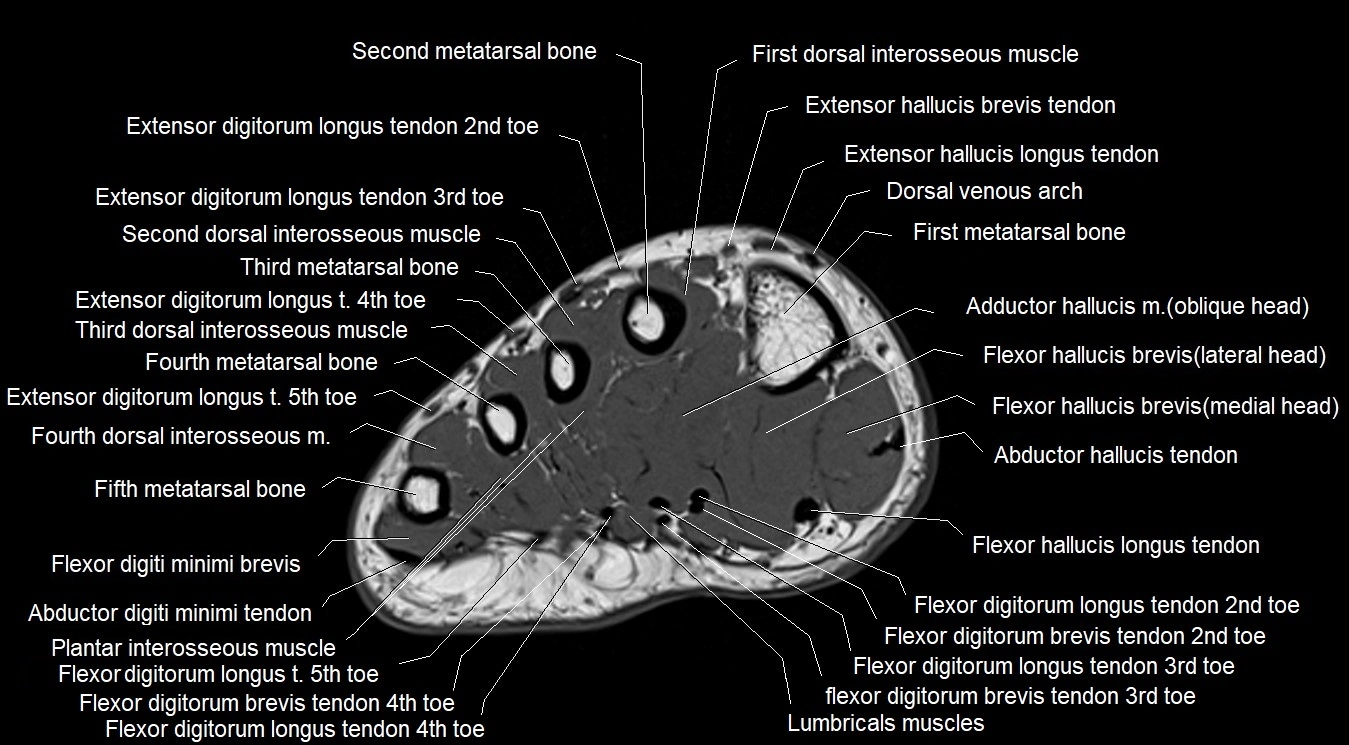

MRI image